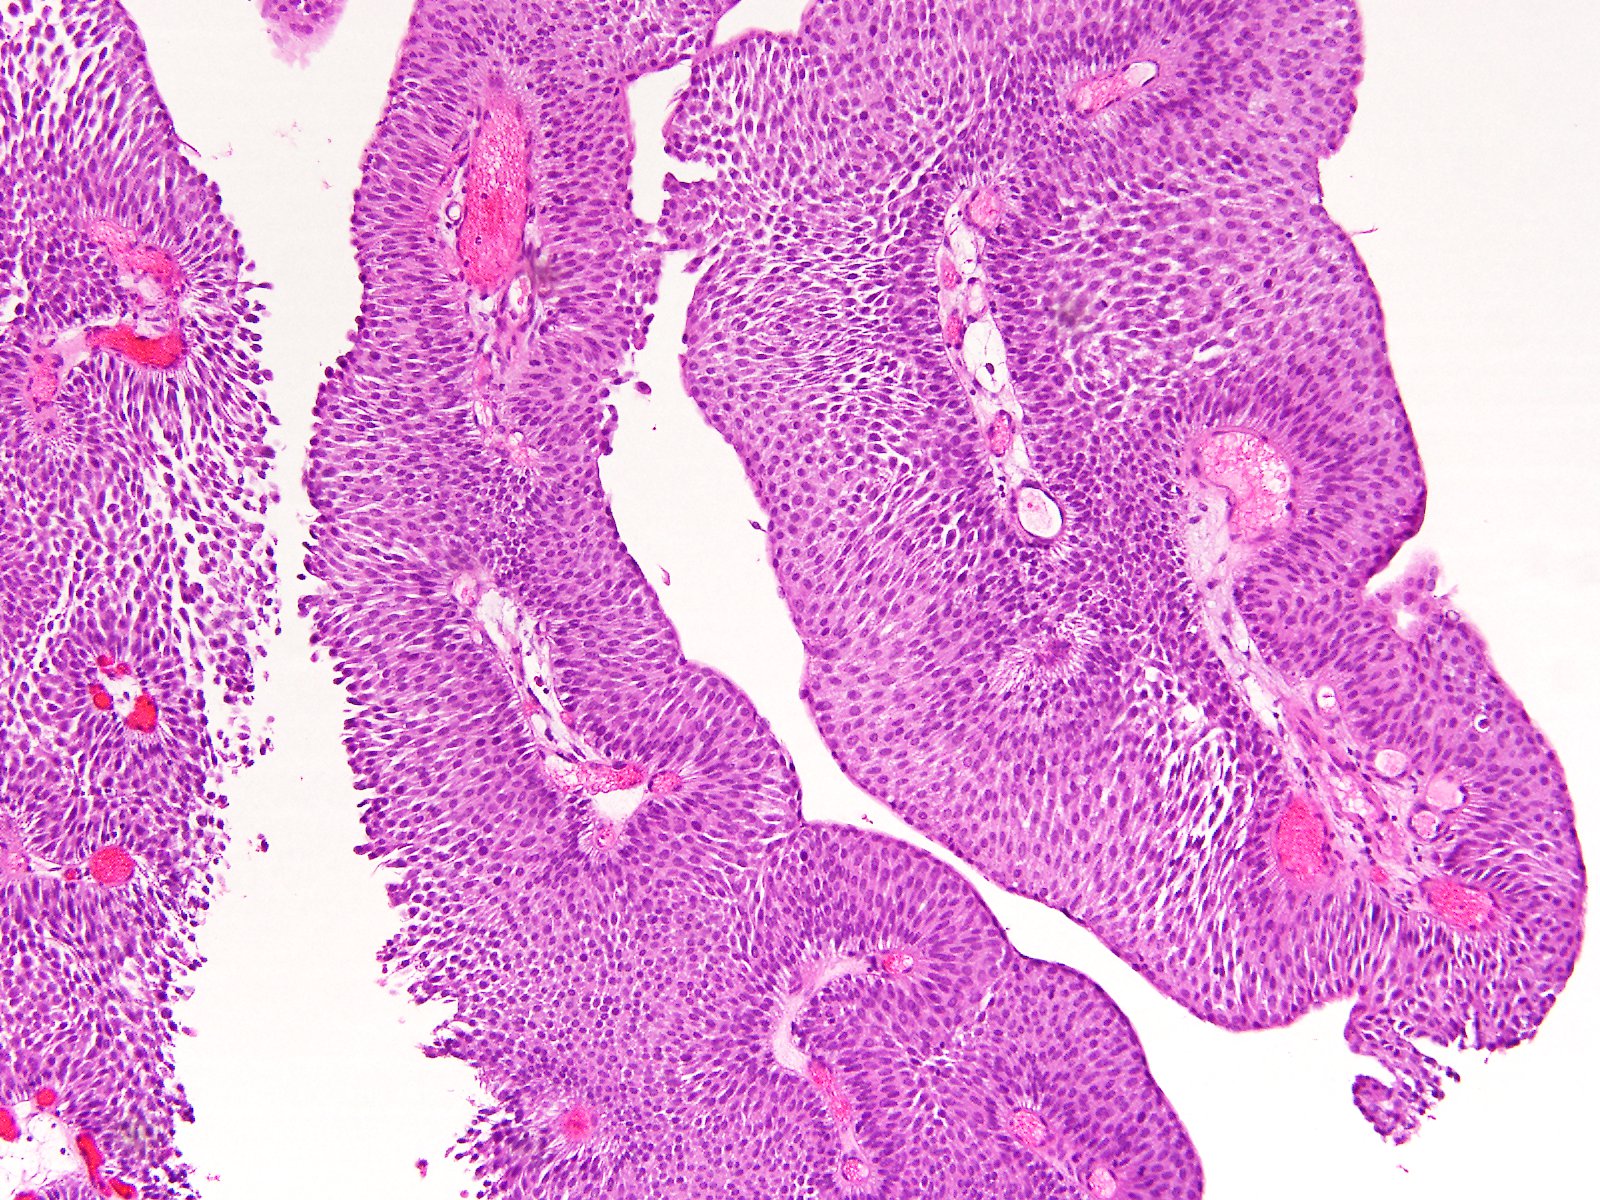

Consensus grade: PUNLMP

87 y/o. Bladder tumor.